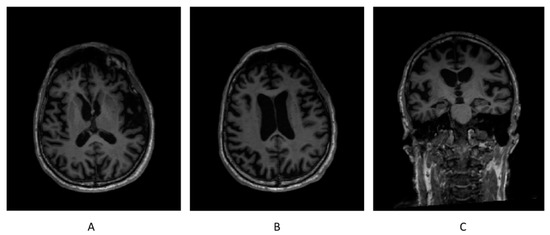

3.5. Brain Morphometry from Structural MRI

Brain morphometry from the structural MRI conducted before the protocol did not find any brain region having a volume out of the normative range. Brain morphometry from the structural MRI attained on 1 October 2021 revealed that the volumes of both gray matter (GM) and white matter (WM) in bilateral frontal lobes were below the normative ranges (TIV-normalized volume of GM in left frontal lobe = 5.28%, and normative range = 5.40–6.59%; TIV-normalized volume of GM in right frontal lobe = 5.28%, and normative range = 5.34–6.46%; TIV-normalized volume of WM in left frontal lobe = 4.07%, and normative range = 4.41–5.67%; and TIV-normalized volume of WM in right frontal lobe = 4.29%, and normative range = 4.37–5.55%), while the volumes of other brain regions were within the normative ranges (Figure 4).

Figure 4.

High-resolution 3D T1-weighted sequence of the structural brain MRI on 1 October 2021. (A) Axial slice displaying normal bilateral basal ganglia, (B) axial slice displaying atrophic bilateral frontal lobes, and (C) coronal slice displaying normal bilateral hippocampus.

The ROIs whose atrophy rates were calculated included both GM and WM in bilateral frontal lobes, bilateral parietal lobes, and bilateral temporal lobes, as well as bilateral insula and bilateral striatum. The atrophy rate of the whole brain was also calculated in contrast with the ROIs. As a result, both the GM and WM in the left frontal lobe, the GM in left parietal lobe and right insula, WM in right frontal lobe, and WM in right parietal lobe showed abnormally high atrophy rates (>4%). Neither the temporal lobes nor striatum had any significant atrophy rate (Table 8).